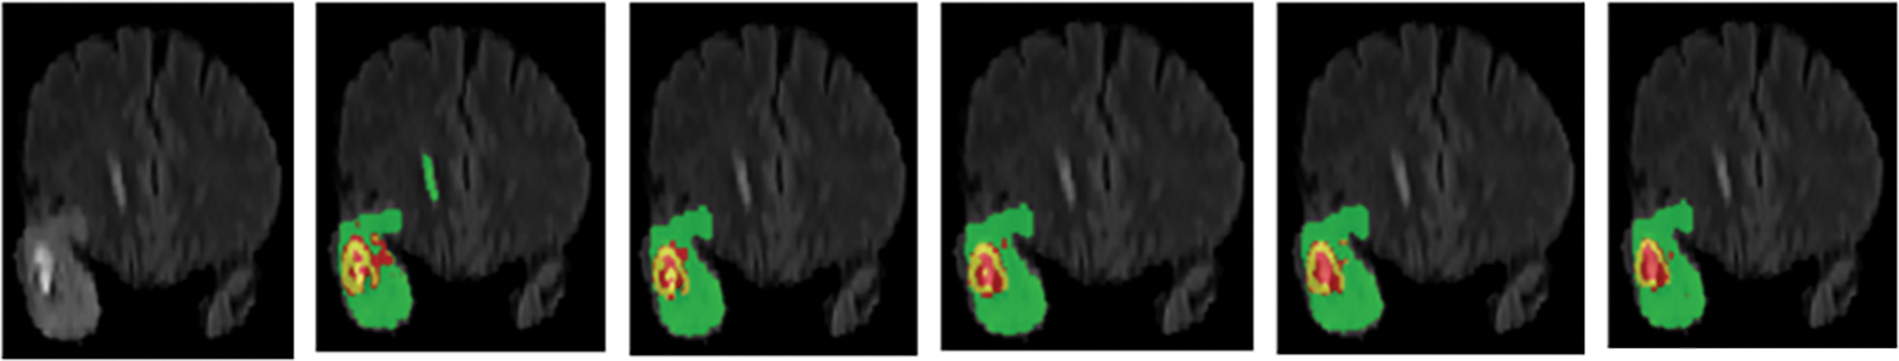

In order to further verify the segmentation performance of the network model, we randomly selected a case (case name: BraTS20_Validation_005) from the validation dataset for qualitative and quantitative analysis. We use five networks (Low-Net, Mid-Net, Hight-Net, Low- + Mid-Net, Low- + Mid- + High-Net) to compare the segmentation results on three different axes: Axial, Coronal, and Sagittal of flair modality, which is depicted in Fig. 2. The three sub-regions segmented by Low- + Mid- + High-Net are the most similar to the target region, and the edge contour lines are also relatively smooth.

Figure 2: Segmentation of different branch networks in the same case. Green, yellow, and red indicate edema, enhancing tumor core, necrotic, and non-enhancing tumor core regions

To further quantitatively assess the segmentation performance of our method, Table 3 presents the Dice scores of the case BraTS20_Validation _005 using the above five networks on the BraTS 2020 validation dataset. The low-level, mid-level, and high-level sub-networks network achieves excellent Dice scores. The above qualitative and quantitative analysis demonstrates that the proposed multi-level parallel network model is effective for brain segmentation of random individual cases.